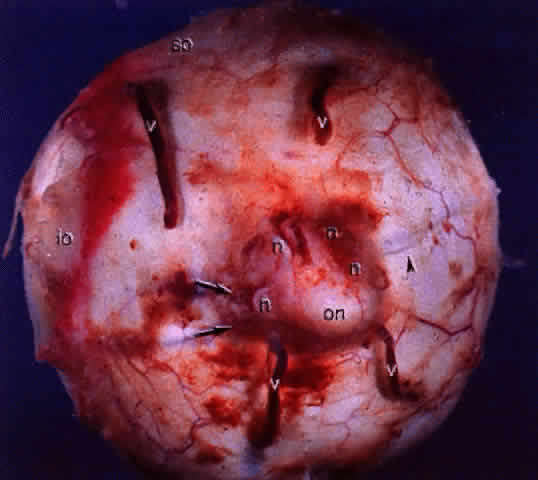

Fig. 14. Gross specimen of posterior of globe shows many of the structures shown in Fig. 13: vortex veins (v), optic nerve (on), muscular tendon of inferior oblique (io), tendon of superior oblique (so), short posterior ciliary arteries (arrows), short posterior ciliary nerves (n), and long posterior ciliary artery and nerve (arrowhead).